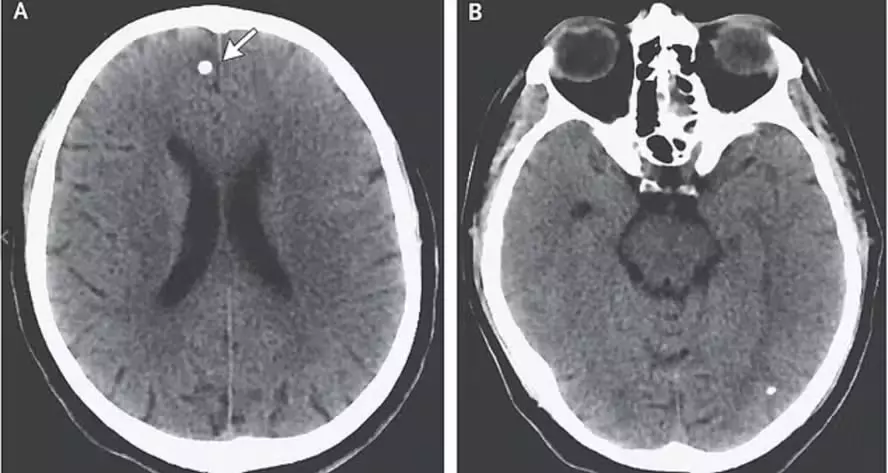

Só depois desse episódio que ela buscou ajuda e, após exames, foi encontrado ovos de tênia no crânio da paciente. Além disso, os médicos notaram que havia o dobro do líquido cefalorraquidiano presente no cérebro, aumentando a pressão na cabeça e causando o pequeno cisto que, se descoberto pouco depois, poderia ser fatal.